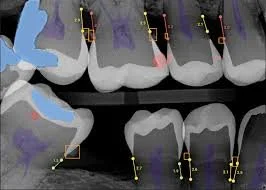

alt="Análisis de radiografía dental asistido por IA con Overjet mostrando caries y pérdida ósea"

Uso de Inteligencia Artificial para el Análisis de Radiografías Dentales

En Creative Toothwork utilizamos Overjet AI para asistir en el análisis y comprensión por parte de los pacientes de radiografías dentales, ayudando a detectar caries, pérdida ósea y otras alteraciones. Esta herramienta complementa el diagnóstico profesional; todas las decisiones de tratamiento son revisadas y aprobadas por nuestros odontólogos. Al recibir atención, usted autoriza el uso de Overjet AI para el análisis de sus radiografías. Toda la información se maneja con confidencialidad y cumpliendo la legislación vigente. Overjet AI no reemplaza el juicio clínico, siendo solo un soporte para mejorar la precisión y seguridad del tratamiento.

At Creative Toothwork Dental Clinic, we integrate advanced AI technology, including Overjet, to enhance radiographic analysis. This allows our dentists to detect dental issues more precisely and deliver personalized treatment plans for every patient.

Our clinic uses Overjet AI to analyze dental X-rays, detecting cavities, bone loss, and other conditions with greater accuracy. This supports clinical decision-making and improves patient outcomes.